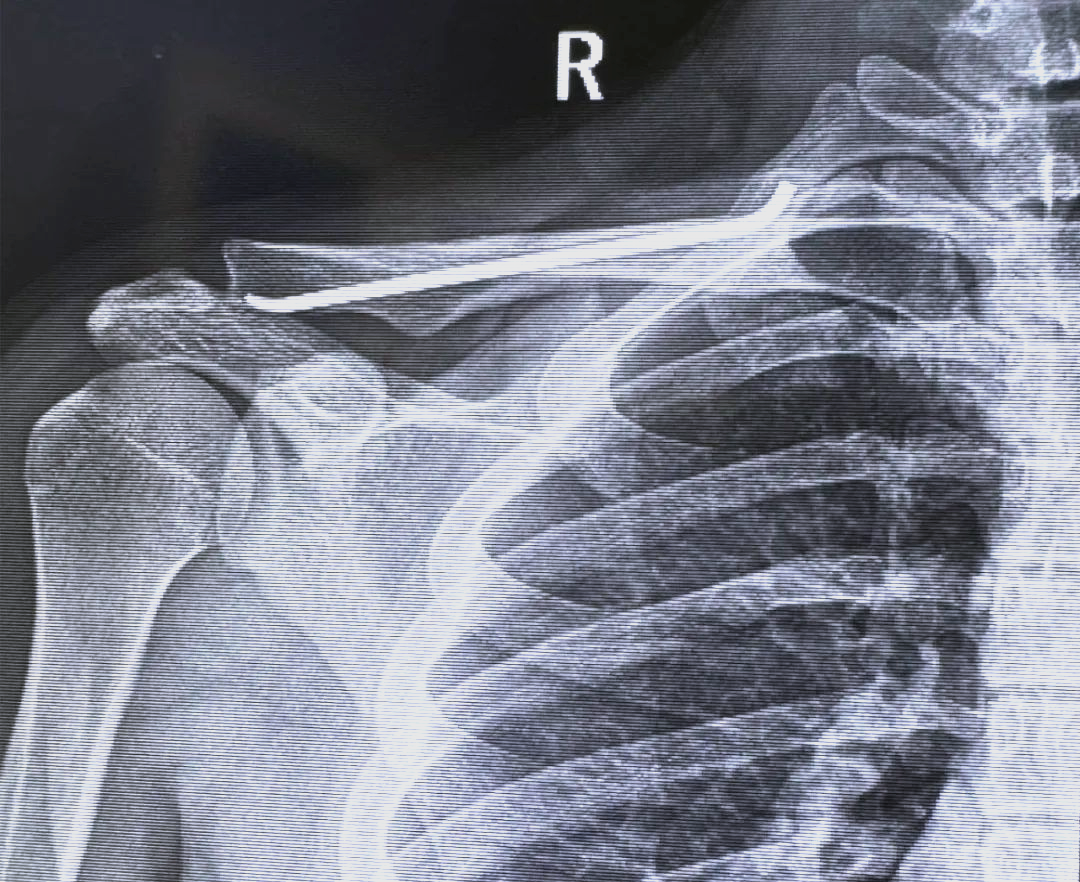

微创技术助力青少年锁骨骨折治疗